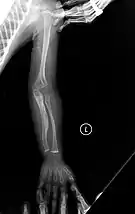

Left forearm

Right forearm

Four X-rays of a 24-year-old American man, who had had more than one hundred bone fractures in his lifetime, and received a childhood clinical diagnosis of type IV–B OI. Genetic diagnosis in 2018 identified a previously uncatalogued pathogenic variant in the gene which encodes proα2(I) chains of type I procollagen, COL1A2, at exon 19, substitution c.974G>A. Due to childhood neglect and poverty, subject never received surgery to implant intramedullary rods. Malunions are evident as the humerus and femur were broken in adolescence but orthopedic care did not follow. Severe scoliosis, as well as kyphosis, are also evident. The unavoidably low contrast in the film is due to a combination of subject's obesity and low bone mineral density (BMD). Subject's BMD Z-score was -4.1 according to results of a dual-energy X-ray absorptiometry (DXA) scan also done in 2018.